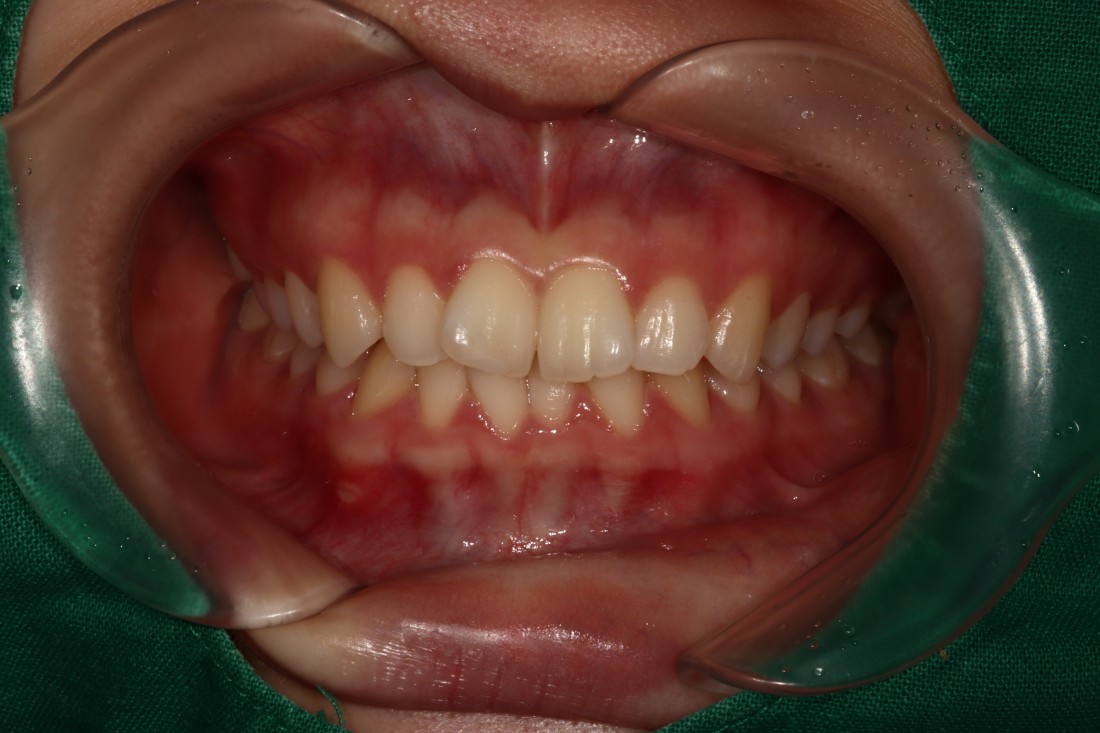

광주 교정치과는

200케이스 넘는 교정사례를

상세하게 공유해드리고 있기 때문에

실력을 믿고 맡기셔도 좋습니다.

더 다양한 교정 전/후 사례는

위의 사진을 클릭하시면

확인하실 수 있습니다.